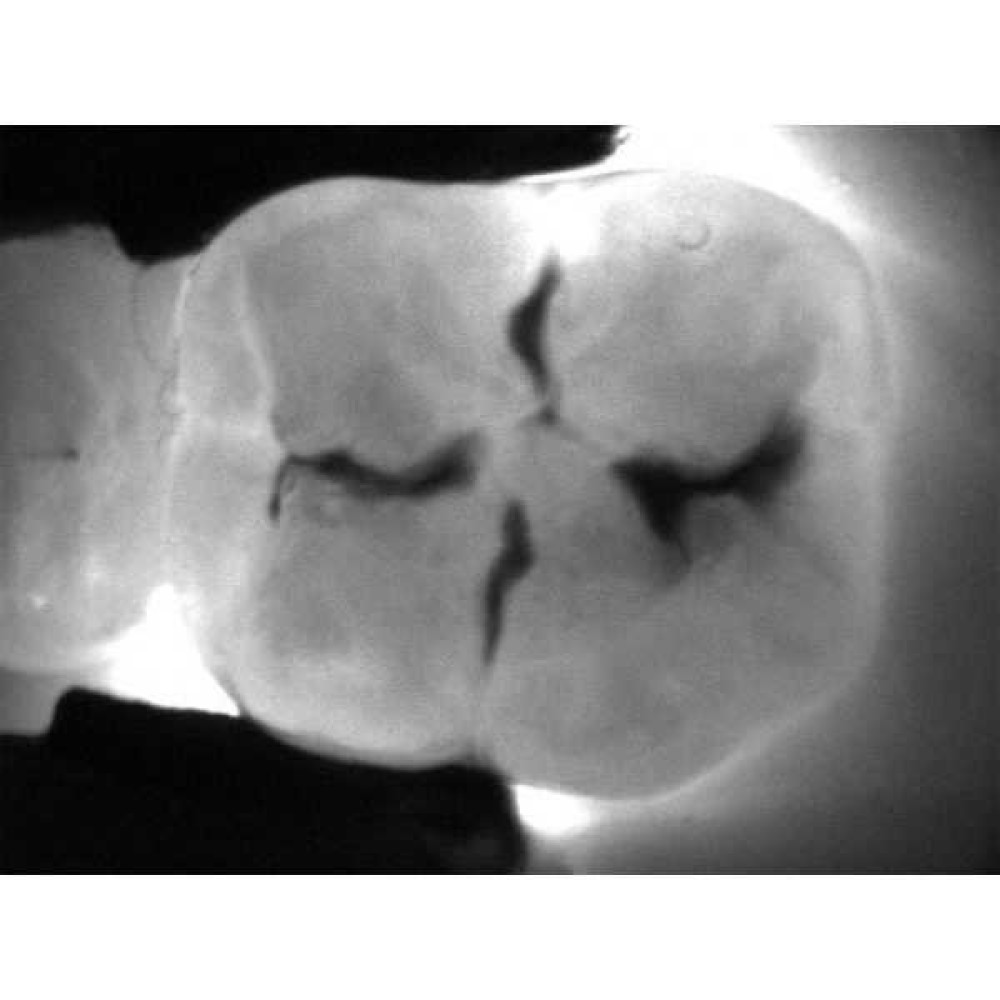

Рентгенограммы и снимки, полученные с помощью KaVo DIAGNOcam, относятся к методам диагностики, прекрасно дополняющим друг друга. С помощью рентгенологической диагностики Вы в дальнейшем сможете беспрепятственно проверить и дополнить данные KaVo DIAGNOcam, исключив часть рентгеновского излучения для пациента. На снимках отчетливо визуализируются структуры коронковой части зуба, располагающиеся выше уровня десневого края. Таким образом, становится возможным раннее распознавание кариеса и проведение профилактического, малоинвазивного лечения. Ваши пациенты будут в восторге!

- Отсутствие наложения теней в контактной области, характерного для рентгенограммы задний план обеспечивает надежную визуализацию.